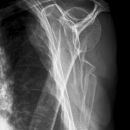

Subcapitale Fraktur und Tuberculum majus